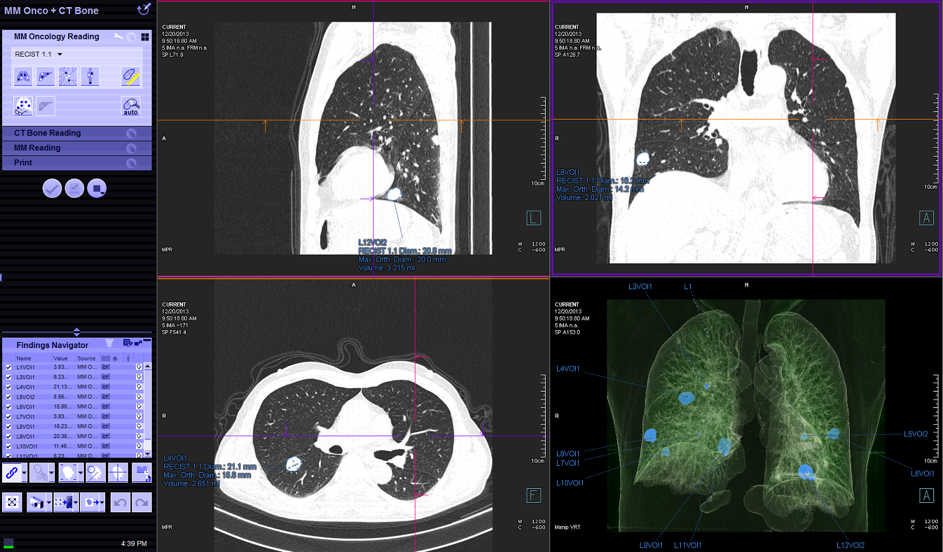

Chụp CT phổi liều thấp:

Liều xạ thấp ở mức 2mSv/1 lần chụp (so với liều chuẩn 6-8 mSv)

Phát hiện sớm các trường hợp ung thư phổi giai đoạn sớm (X-quang có thể âm tính) giúp giảm tỷ lệ tử vong .

Tác dụng trong việc sàng lọc ung thư phổi, giúp giảm tỷ lệ tử vong và tăng thời gian sống thêm sau 5 năm ở bệnh nhân ung thư phổi

Hình 11. Chụp CT phổi liều thấp

Hình 12. LDCT tổn thương ở phổi(P): nốt đặc, nốt bán đặc, nốt kính mờ. Nốt kính mờ có thể sẽ chuyển thành nốt bán đặc sau 5 năm, nếu có tình trạng này thì nguy cơ ung thư phổi rất cao.